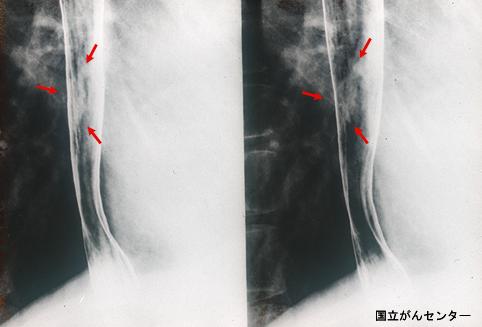

Criteria of Hist.ClassificationMalignant epithelial tumor/Squamous cell carcinoma

LocationEsophagus/Lower third

Technique, MethodX-ray

Macroscopic TypesType 0/IIc (IIc) Superficial depressed type

Size10 - 14

Depth of Tumor Invasionmuscularis mucosa